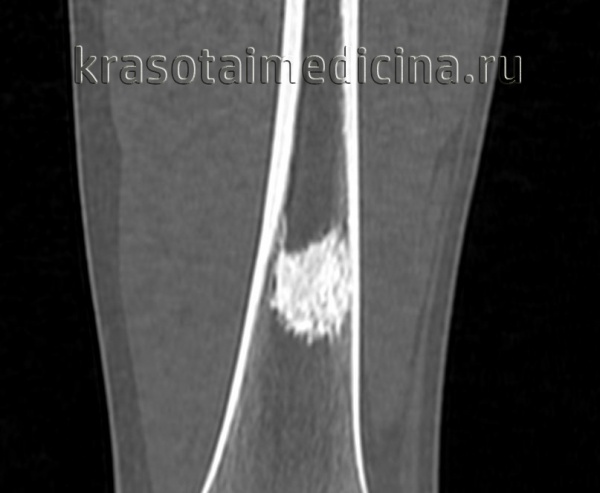

- Рентгенография кости. На снимках визуализируется кистообразные изменения или неоплазия в виде «мыльных пузырей» в метафизарной зоне. Признаки общего остеопороза отсутствуют, вокруг измененного участка может просматриваться остеосклероз. Границы доброкачественной ГКО более четкие, но из-за местно-агрессивного роста при значительном размере возможно появление «костного козырька». Выраженная периостальная реакция нехарактерна. Злокачественная остеокластома имеет нечеткую структуру. На снимках рано обнаруживается разрушение кортикального слоя.

- КТ и МРТ кости. Компьютерная томография дает более четкое представление о форме, размерах, границах гигантоклеточной опухоли, в сомнительных случаях позволяет подтвердить или опровергнуть разрыв коркового слоя. В ходе магнитно-резонансной томографии исследуют интрамедуллярный и кистозный компоненты, оценивают состояние окружающих мягких тканей, расположение сосудов и нервов. Методики помогают выбрать оптимальный вариант хирургического вмешательства, спланировать операцию.

КТ левого бедра. Объемное образование (оссифицированная энхондрома) в нижней трети диафиза бедренной кости.